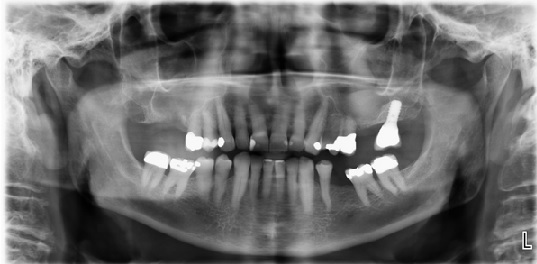

画像 1. 右側上顎洞の口腔前庭部交通と慢性副鼻腔炎…